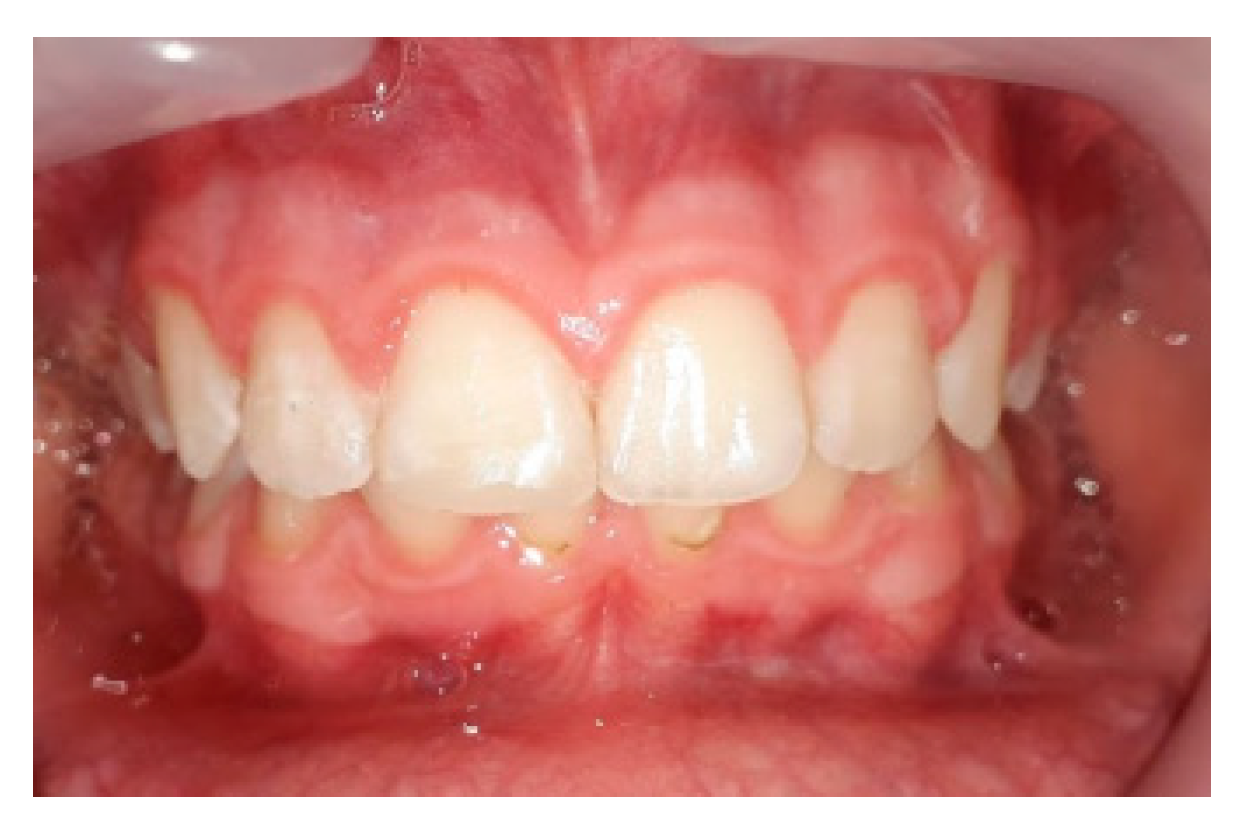

3.1. Outcomes of the Treatment at the One-Year Follow-Up

3.3. Situation of the Treatment after Two Years